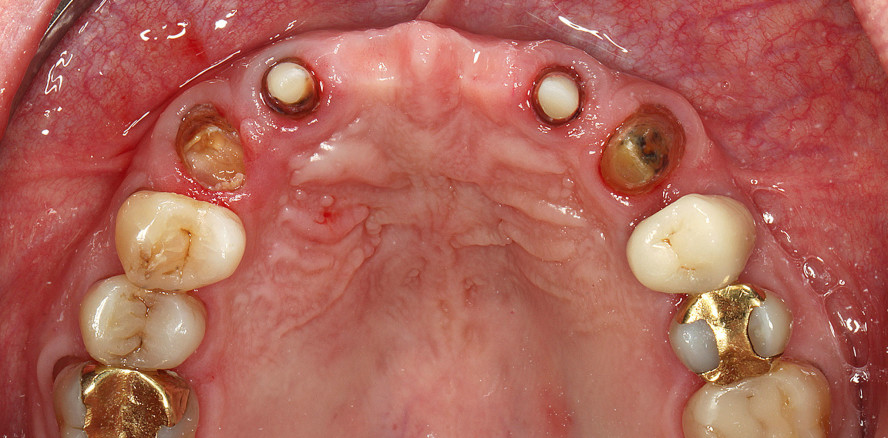

Der Wunsch des Patienten war eine festsitzende Restauration in der Front sowie eine Komplettsanierung im Oberkiefer bei maximalem Erhalt seiner natürlichen Zähne. Neben verschiedenen Defekten in der Zahnhartsubstanz zeigte sich bei der klinischen und röntgenologischen Inspektion als primärer Auslöser für die erhöhte Beweglichkeit der vorhandenen Brücke eine horizontal verlaufende Kronen-Wurzel-Fraktur im oberen Drittel von Zahn 13. Während sich Zahn 13 jedoch als erhaltungswürdig mit langfristig guter Prognose darstellte und daher wurzelbehandelt werden sollte, war bei Zahn 22 aufgrund einer apikalen Beherdung das Risiko zu hoch, ihn auch nach einer Revision als Pfeiler in eine Neuversorgung einzubinden. Zahn 12 wies horizontale Risse auf und die geringe restliche Zahnsubstanz schränkte seine Prognose ein. In Absprache mit dem Patienten sollten daher die Zähne 16 bis 13 – nach dessen intentioneller Replantation – und 23 bis 26 neu überkront werden.3 Anterior war nach Extraktion der beiden Zähne 12 und 22 und Sofortimplantation eine implantatgetragene Brücke vorgesehen. Die Implantate sollten unter einem Provisorium von 16 auf 26 offen einheilen.

Vor der Implantation wurden die beiden oberen lateralen Inzisivi extrahiert. Dabei können durch ein schonendes Vorgehen und eine vorsichtige Behandlung des marginalen Weichgewebes sowie des Alveolarknochens die Resorptionsvorgänge nach der Extraktion positiv beeinflusst werden, wohingegen orovestibuläre Luxationsbewegungen zu einer Kompression oder sogar Fraktur der dünnen vestibulären Lamelle führen können.8 Nach der Extraktion werden mit einer sorgfältigen Kürettage Geweberückstände, die die Osseointegration gefährden und zu Infektionen führen könnten, aus der Alveole entfernt. Ebenfalls noch vor dem implantatchirurgischen Eingriff wurden die Zähne 14 bis 16 und 24 bis 26 für die Aufnahme des Provisoriums und die spätere Neuversorgung entsprechend präpariert.

Die dreidimensionale Positionierung der beiden Ankylos-Implantate erfolgte auf Grundlage einer DVT-Aufnahme, auf der auch gut das residuale Knochenangebot bestimmt werden konnte. Lappenbildung und vertikale Entlastungsinzisionen waren nicht notwendig, sodass es nicht zu Irritationen des Weichgewebes und möglicher Narbenbildung kommen konnte.11 Beide Implantate – Durchmesser von 3,5 mm bei 11 mm Länge – wurden gemäß Protokoll in mesiodistaler, koronoapikaler und orofazialer Richtung in das sogenannte „ästhetische Fenster“ mit palatinalem Knochenkontakt und vestibulärem Spalt sowie circa 1 bis 2 mm subkrestal inseriert.12,13 Zu weit nach bukkal inserierte oder zu stark nach bukkal angulierte Implantate bergen das Risiko von Weichgewebsrezessionen und die Gefahr eines gräulichen Durchschimmerns des Implantats. Nachfolgende chirurgische Eingriffe zur Deckung führen in solchen Fällen meist nicht zum gewünschten Ergebnis.4,14,15